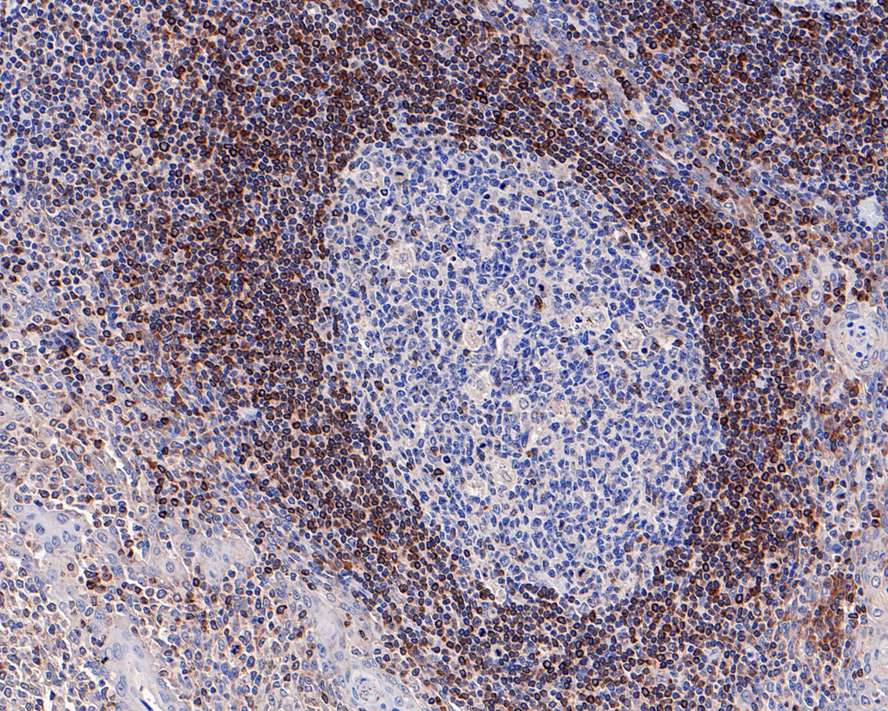

Immunohistochemical analysis of paraffin-embedded human tonsil tissue with Rabbit anti-Bcl-2 antibody (HA721235) at 1/2,000 dilution.

The section was pre-treated using heat mediated antigen retrieval with Tris-EDTA buffer (pH 9.0) for 20 minutes. The tissues were blocked in 1% BSA for 20 minutes at room temperature, washed with ddH2O and PBS, and then probed with the primary antibody (HA721235) at 1/2,000 dilution for 1 hour at room temperature. The detection was performed using an HRP conjugated compact polymer system. DAB was used as the chromogen. Tissues were counterstained with hematoxylin and mounted with DPX.